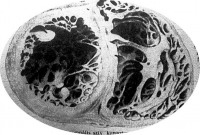

Az érfal rugalmasságának elvesztése jellemző arra az érbetegségre, amelynek nevét a legjobban ismeri a közönség is: az érelmeszesedésre. Azt szokták mondani, hogy az öregkor jellegzetes betegsége ez. Hogy nem így van: bizonyítják azok az aggastyánok, akiknek érfalain az elmeszesedésnek, megkeményedésnek még a nyomaival sem találkozunk.